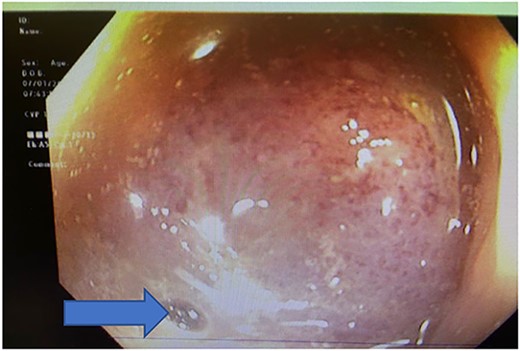

On hospital Day 2, patient underwent diagnostic sigmoidoscopy. We identified a bulky mass obscuring the lumen at 5 cm from the anal verge (Fig. 3). During hospital Day 3, patient was tolerating a clear liquid diet. A 1.5 Tesla Pelvic MRI demonstrated an apple core lesion, staged at least mT3N0, sparing anal sphincters, as shown in Fig. 4. Biopsy pathology identified adenocarcinoma. During hospital Day 4, oncology was consulted and recommended neoadjuvant chemoradiation therapy as outpatient.

Colonoscopy showing bulky mass obscuring the lumen at 5 cm from the anal verge, blue arrow pointing at the miniscule lumen.